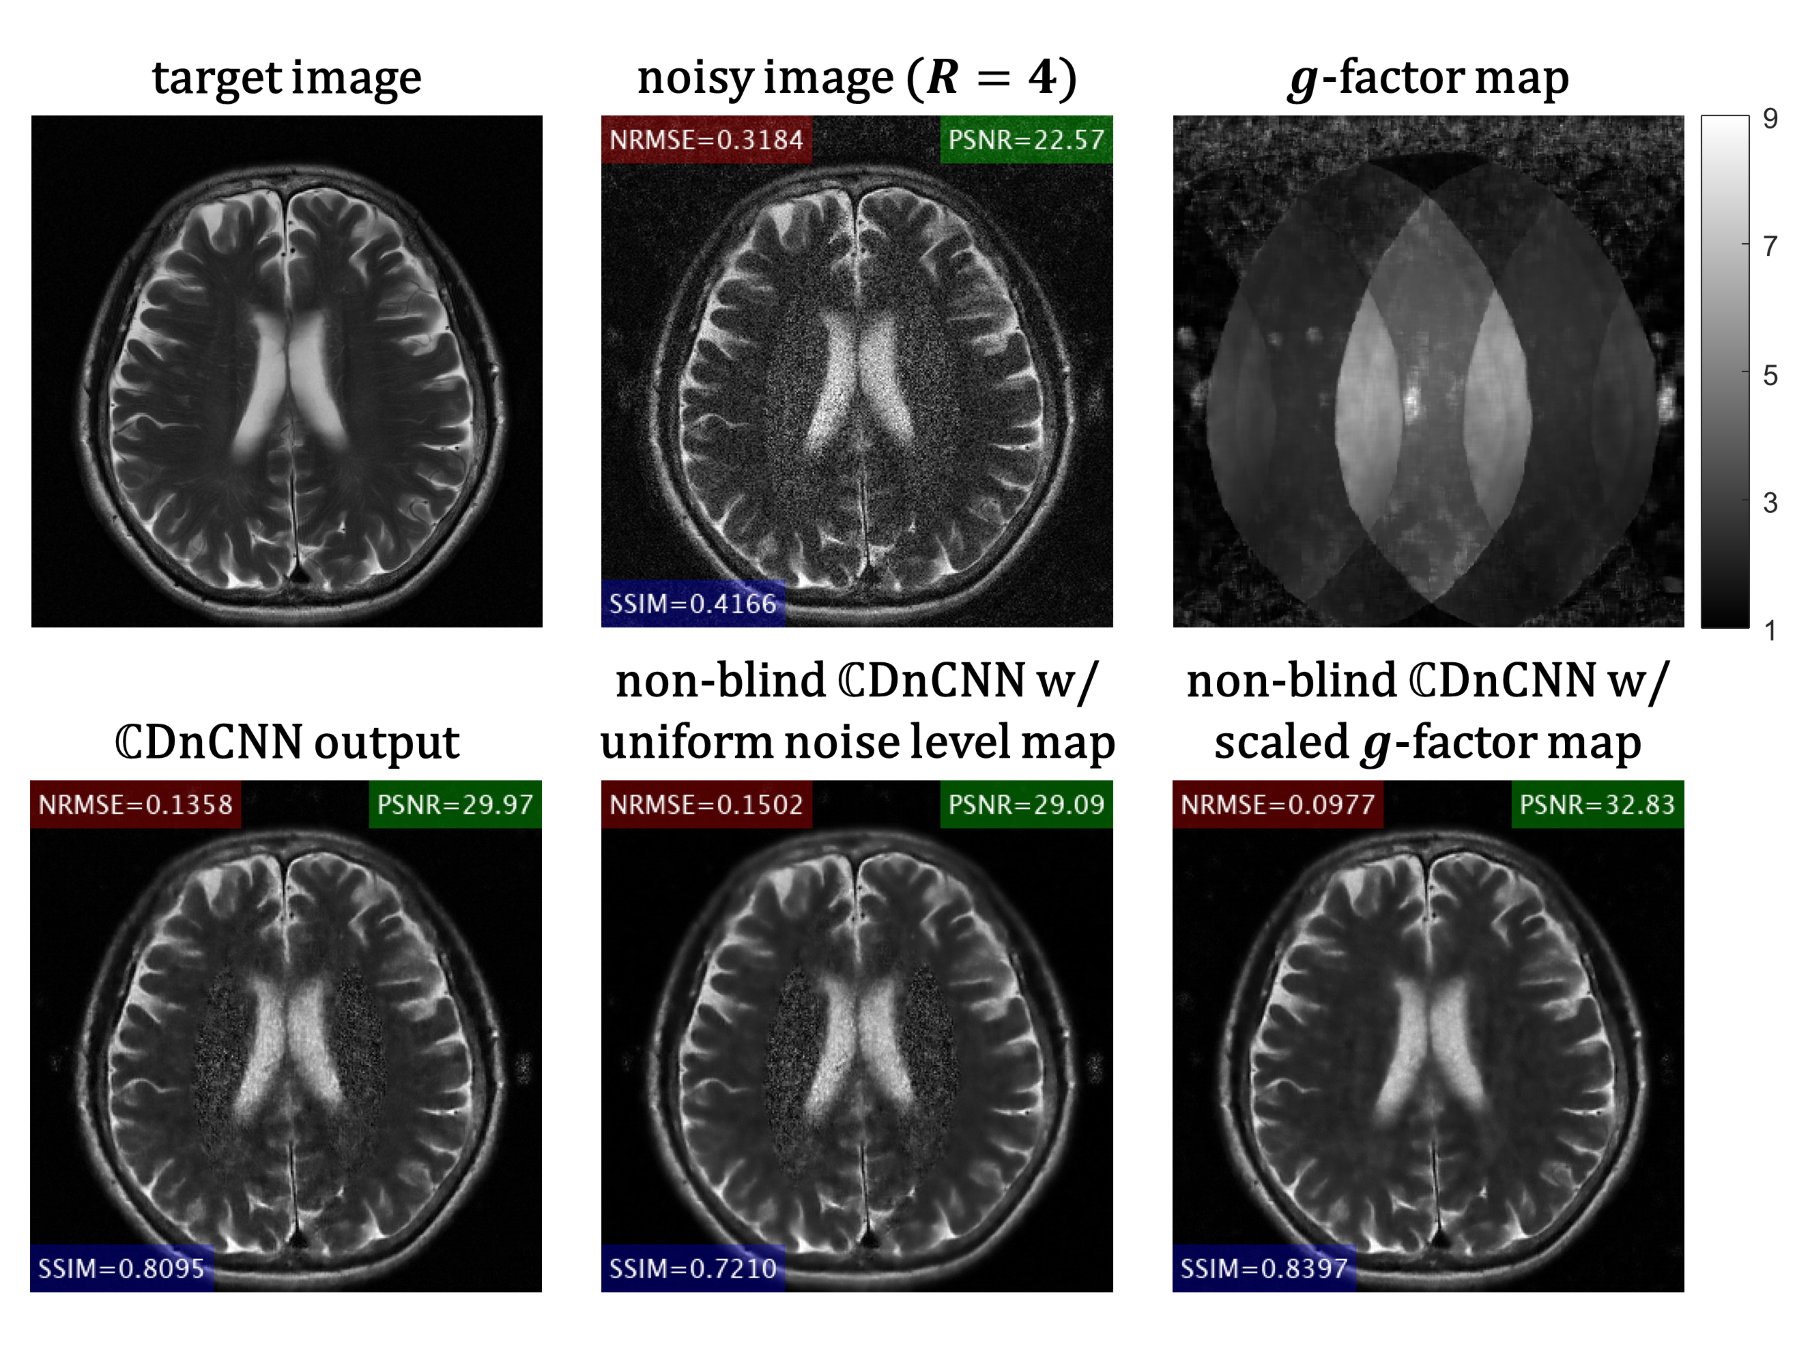

Figure 2A shows the quantitative evaluation results at different noise levels. The proposed non-blind $$$\mathbb{C}$$$DnCNN outperforms other methods with lower NRMSE, and higher PSNR and SSIM. Figure 2B shows representative slices from the testing dataset. The output of non-blind $$$\mathbb{C}$$$DnCNN shows reduced noise and less visual blurring compared to other methods. The computational cost for each method is summarized in Table 1. Figure 3 shows the network performance on SENSE reconstructed image. With scaled g-factor map as the noise level map, non-blind $$$\mathbb{C}$$$DnCNN successfully removed the spatially variant noise, while other methods failed at the center regions with large g-factor. Figure 4 shows the network performance on testing data out of the training distribution. The network is able to denoise the images and shows good generalization capability.

Figure 3 Network performance on SENSE reconstructed image with spatially variant noise.